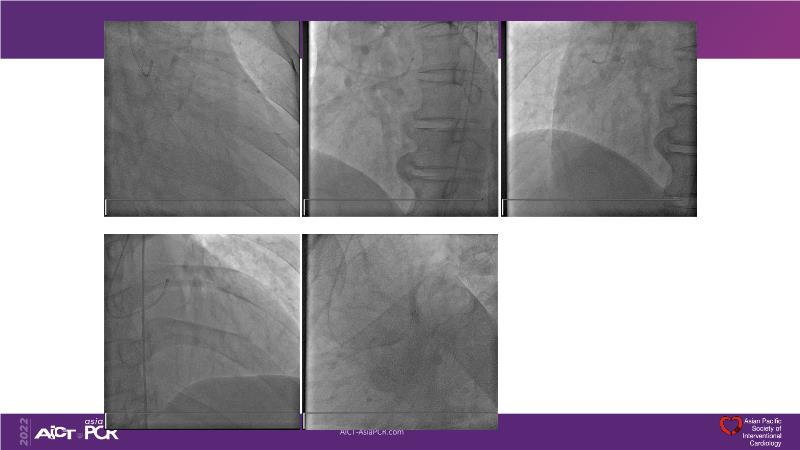

- To define the use of OCT in PCI of complex coronary lesions